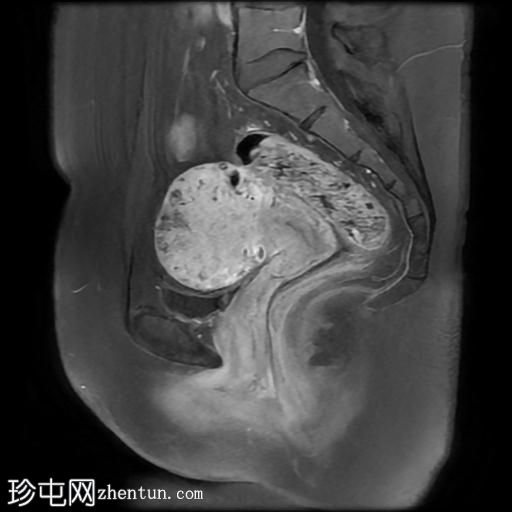

矢状位

T2加权像

盆腔MRI显示双侧子宫旁多条迂曲静脉,自子宫肌层延伸至盆腔。

此外,左侧附件可见两个充满液体的单纯性囊肿,大小分别约为31 mm和32 mm;右侧附件可见一个卵泡囊肿,大小约为19 mm。

影像学特征符合盆腔充血综合征的诊断,患者为35岁女性,有慢性盆腔疼痛和痛经病史。